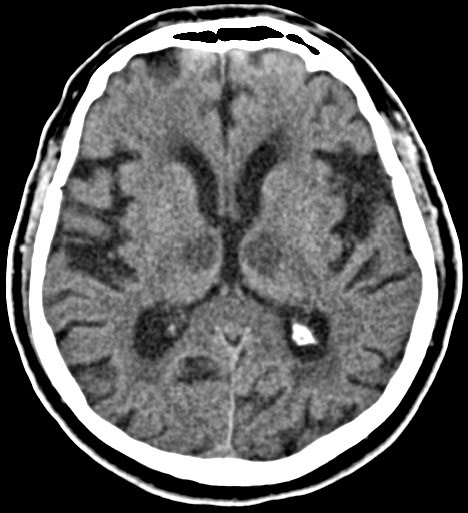

methanol toxicity

bilateral putaminal hemorrhages/necrosis

can also see damage to optic nerves